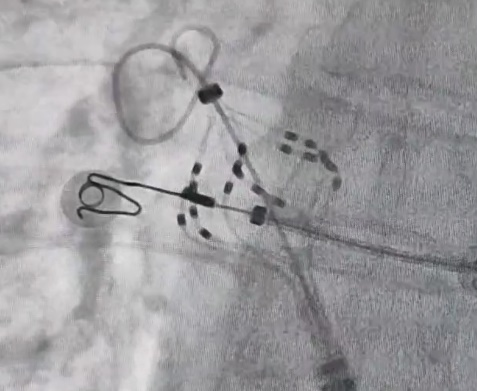

术中均直接采用脉冲电场消融导管自身标测电极进行了电位标测,消融即刻四根肺静脉电位消失。在术中患者发生房颤,行右上肺静脉电位隔离后房颤终止。所有肺静脉消融完成后观察20min,行肺静脉-心房双向传导阻滞测试,所有肺静脉轻松达到电隔离状态,消融即刻成功,手术结束。整台手术用时不到2h,其中导管左房操作时间40min,安全高效。手术的成功标志着我院心内科团队在房颤治疗上的又一突破,为区域房颤患者的有效救治再添利器。

消融前后腔内电位对比图